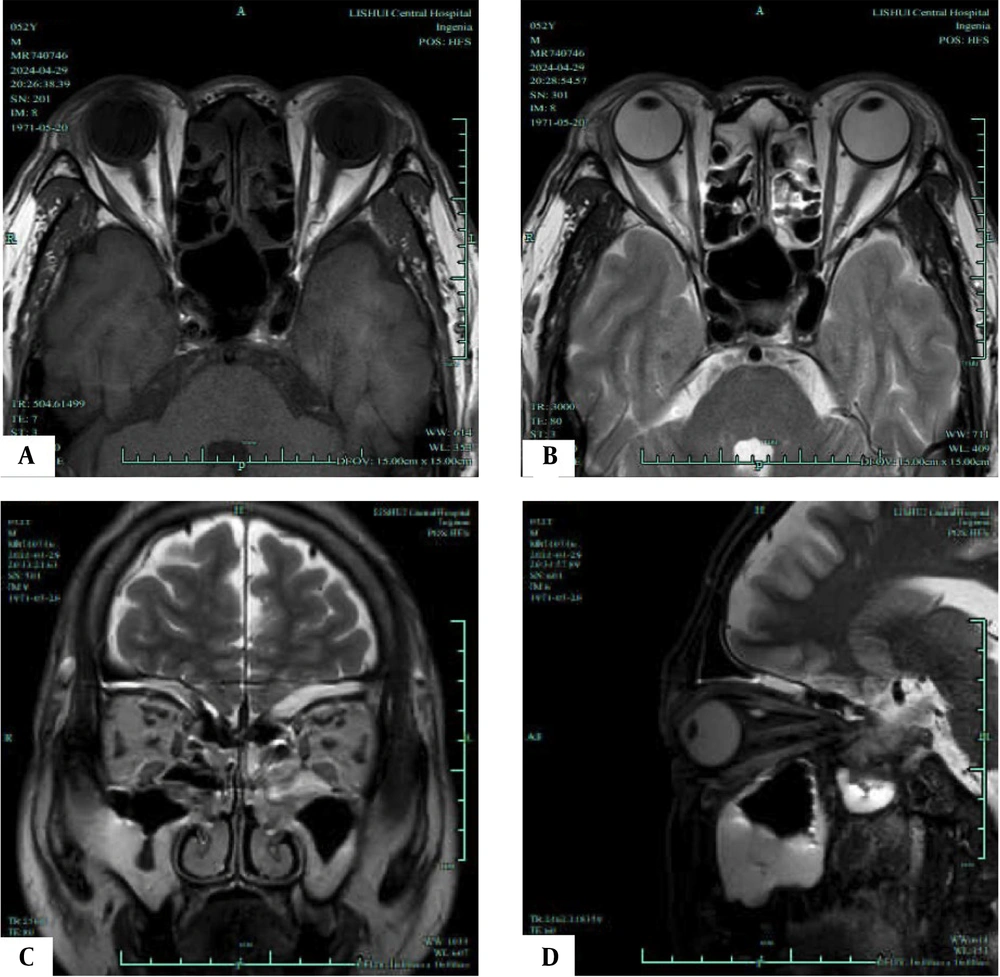

Likewise, as illustrated in Figure 4, the progression group exhibited significantly higher average EOM water fraction (0.96 ± 0.18 vs. 0.82 ± 0.15), average EOM water signal intensity (409.55 ± 115.72 vs. 330.86 ± 105.96), average EOM fat signal intensity (104.20 ± 13.88 vs. 80.26 ± 9.96), average lacrimal gland signal intensity (89.62 ± 11.32 vs. 79.38 ± 10.25), average of unilateral four EOM fat fractions (69.96 ± 9.15 vs. 51.80 ± 7.90), average EOM T2 value (81.75 ± 8.32 vs. 76.90 ± 7.14), and average EOM cross-sectional area (54.65 ± 7.88 vs. 42.50 ± 6.98) compared to the non-progression group. These differences were statistically significant (t = 3.711, 2.734, 8.858, 4.123, 9.290, 2.738, 7.116, P < 0.05).